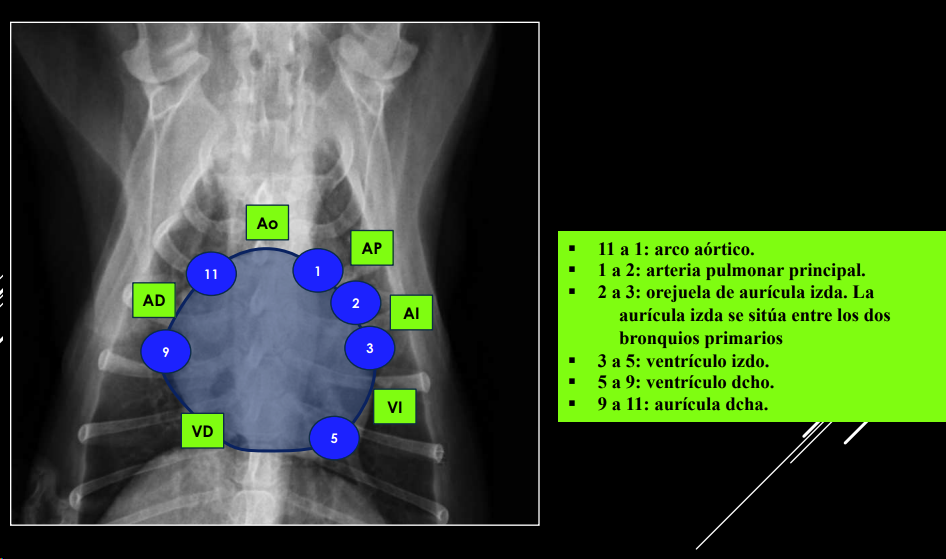

POSICIÓN DE CÁMARAS Y GRANDES VASOS (“analogía del reloj”)

Se puede comparar la silueta cardíaca con la esfera de un reloj <analogía del reloj=,utilizando los intervalos horarios para la localización de las cámaras cardíacas y de los grandes vasos.

Proyección DV:

- 11–1: arco aórtico.

- 1–2: arteria pulmonar.

- 2–3: orejuela AI.

- 3–5: ventrículo izdo.

- 5–9: ventrículo dcho.

- 9–11: aurícula dcha.

Proyección LL:

- Craneodorsal: aorta y atrio derecho.

- Craneoventral: ventrículo derecho.

- Caudodorsal: atrio izquierdo.

- Caudoventral: ventrículo izquierdo.

ALTERACIONES DE CÁMARAS CARDÍACAS

- AI: elevación dorsal tráquea, protusión 2–3 h (DV).

- AD: desplazamiento dorsal tráquea, protusión 9–11 h.

- VI: incremento altura silueta, protusión 3–5 h (DV).

- VD: forma “D invertida”, aumento cardioesternal.

- Pericardio: distensión → silueta globosa, puede contactar bilateralmente con márgenes costales.